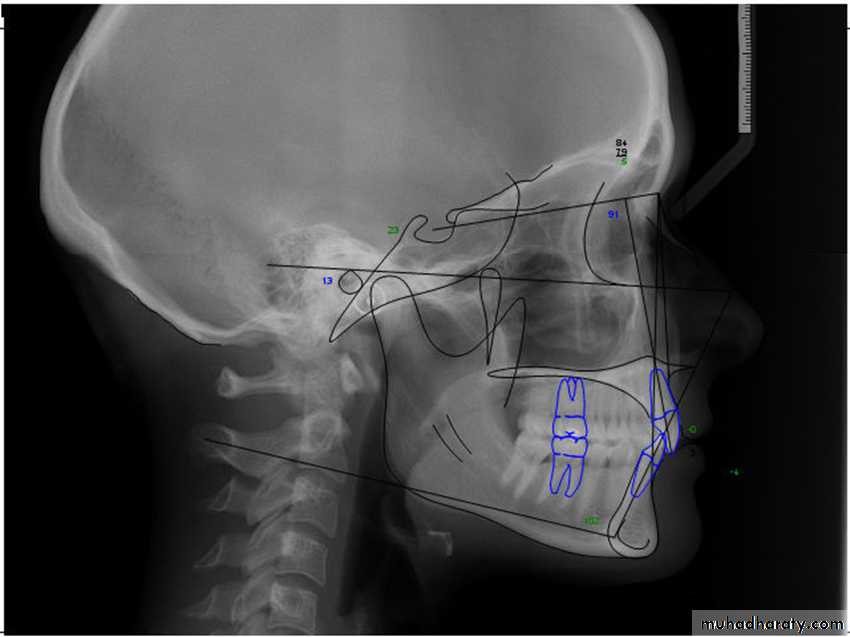

• Cephalometric x-rays provide for standardized skull and/or facial views that allow for comparison over time to assess growth in an individual and for comparison of that individual against standardized population norms. Skeletal views can be obtained in lateral and frontal views.

Lateral cephalometric landmarks

Lateral cephalometric x-ray also allows the dentition to be related to each other, and each can be related to its own skeletal base, the maxilla, and the mandible.

Frontal cephalometric x-ray allows for assessment of the degree of facial asymmetry.

For the surgeon, the analysis must be clinically workable, simple to use, and directly relatable to the skeletal elements that can be repositioned.